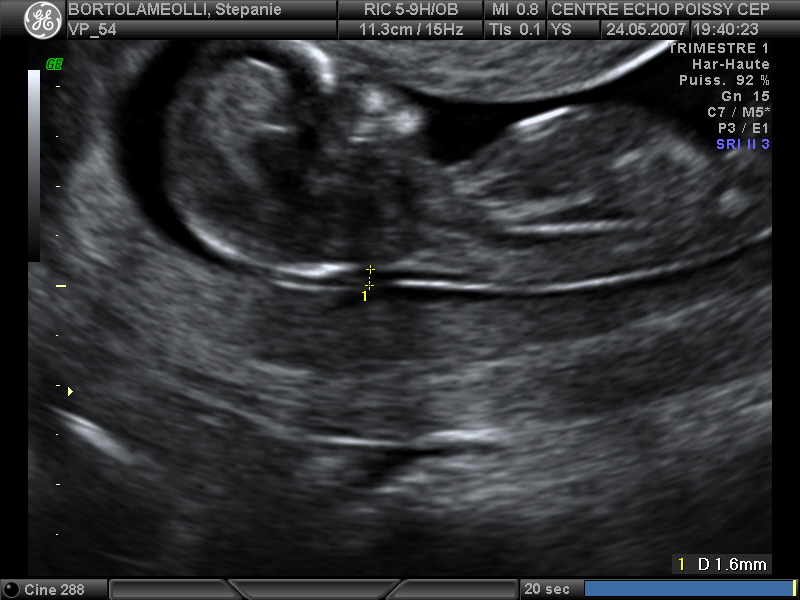

Echographies

Mai 2007